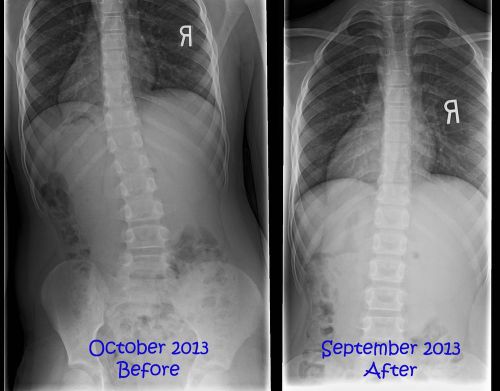

Learn Heel Lifts and Scoliosis for Chiropractors DVD